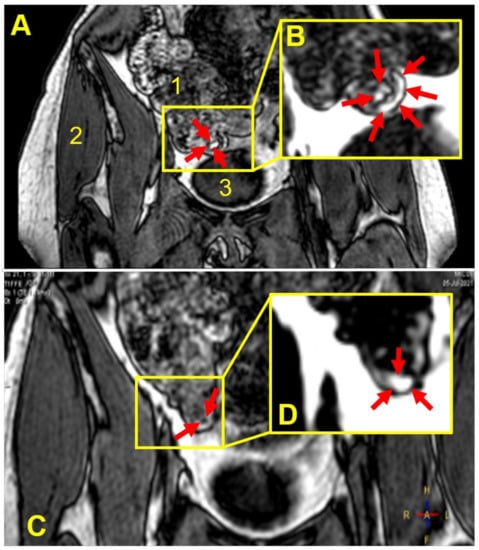

2. Materials and Methods

3.3. Capsule Imaging Studies In Vivo